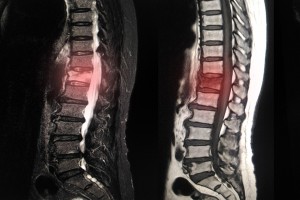

椎间盘突出

( 腰椎椎间盘突出)

腰部椎间盘的破裂或凸出,可能会压迫神经并引起疼痛。